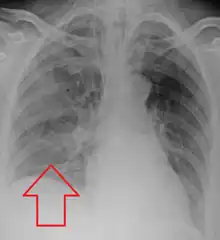

Aspiration pneumonia in a ventilated person with a central line and nasogastric tube

Aspiration pneumonia is typically diagnosed by a combination of clinical circumstances (people with risk factors for aspiration) and radiologic findings (an infiltrate in the proper location).[1] A chest x-ray is typically performed in cases where any pneumonia is suspected, including aspiration pneumonia.[18] Findings on chest x-ray supportive of aspiration pneumonia include localized consolidation depending on the patient's position when the aspiration occurred.[18] For example, people that are supine when they aspirate often develop consolidation in the right lower lobe of the lung.[18] Sputum cultures are not used for diagnosing aspiration pneumonia because of the high risk of contamination.[19] Clinical symptoms may also increase suspicion of aspiration pneumonia, including new difficulty breathing and fever after an aspiration event.[6] Likewise, physical exam findings such as altered breath sounds heard in the affected lung fields may also be suggestive of aspiration pneumonia.[6] Some cases of aspiration pneumonia are caused by aspiration of food particles or other particulate substances like pill fragments; these can be diagnosed by pathologists on lung biopsy specimens.[20]